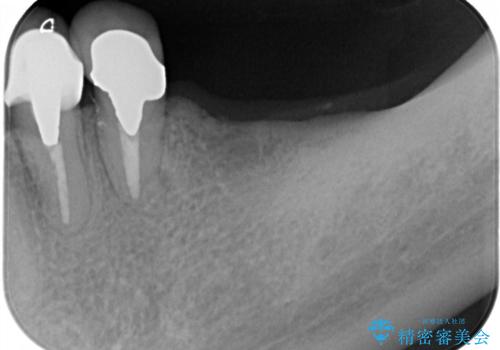

左上は、抜歯とブリッジ治療を行いました(抜歯前に医師と対診)。

左下は、現在も抗がん治療を続けているため、観血的処置(インプラントなどの外科)はなるべく避けたいとのことで入れ歯を希望されました。それに伴い、入れ歯を支える歯のクラウンやりかえも行いました。

患者様はインプラント等の外科処置は希望されなかったため、セラミックと義歯で治療を行いました。

義歯を製作する際は、支えとなる歯の治療も同時に行うことで、義歯の製作が容易になります。